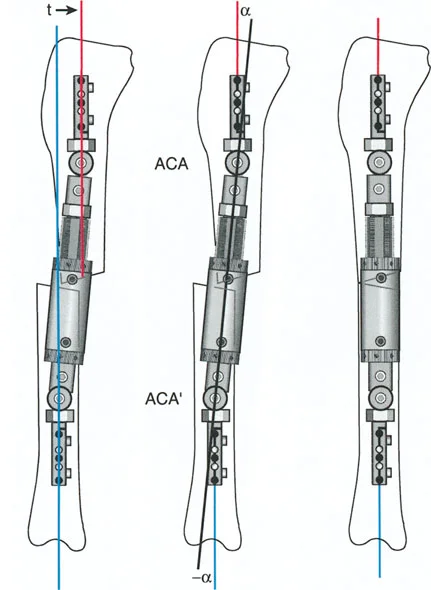

قواعد بالي لقطع العظم (Osteotomy Rules) في وضع الأجهزة

فهم قواعد بالي لقطع العظم أمر لا غنى عنه لتخطيط الإطار:

- قاعدة قطع العظم 1: عندما يمر قطع العظم ومحور تصحيح الانحراف (ACA) كلاهما عبر مركز دوران الانحراف (CORA)، فإن نهايات العظم ستنحرف دون ترجمة (انزياح). يتم استعادة المحور الميكانيكي، وتظل نهايات العظم متقاربة تمامًا، مما يخلق تصحيحًا كلاسيكيًا "إسفينيًا مفتوحًا" أو "إسفينيًا مغلقًا".

- قاعدة قطع العظم 2: عندما يمر محور تصحيح الانحراف (ACA) عبر مركز دوران الانحراف (CORA)، ولكن يتم إجراء قطع العظم على مستوى مختلف (غالبًا بسبب ضعف جودة العظم عند CORA أو مشاكل في الجلد)، فإن نهايات العظم ستنحرف وتخضع لترجمة محسوبة ومقصودة لإعادة محاذاة المحور الميكانيكي.

- قاعدة قطع العظم 3: (للاكمال) عندما يمر قطع العظم عبر مركز دوران الانحراف (CORA)، ولكن يتم وضع محور تصحيح الانحراف (ACA) خارج CORA، سيتم إنشاء تشوه ترجمة جديد، وهو خطأ شائع في وضع المفصلات غير المخطط له جيدًا.

في المنشآت القريبة من المفصل، غالبًا ما نعتمد على قاعدة قطع العظم 2. نظرًا لأنه لا يمكننا قطع العظم بأمان عند خط المفصل تمامًا (مركز دوران الانحراف CORA)، فإننا نقطع العظم في مستوى أدنى في منطقة الميتافيسيس. بعد تحقيق التصحيح الزاوي عبر المفصلات (محور تصحيح الانحراف ACA)، يتم إعادة محاذاة خطوط المحور الميكانيكي بشكل مثالي، ولكن نهايات العظم في موقع قطع العظم تتحرك بالنسبة لبعضها البعض.